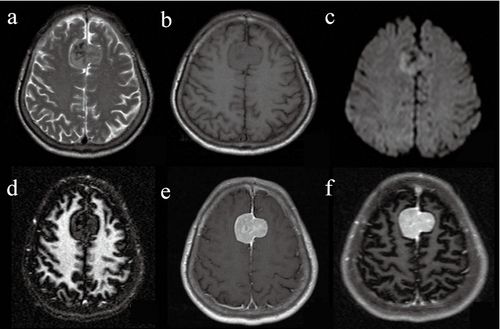

脑白质病变影像诊断

脑白质成像影像特征与常规mri比较